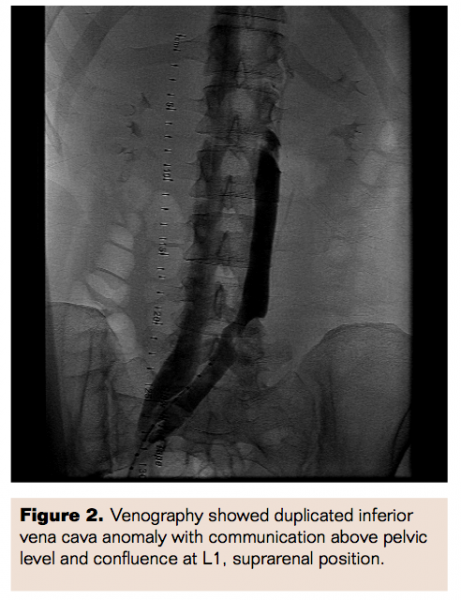

She was then brought back to the catheterization laboratory the next day for venography and her residual thrombus burden was assessed. Venography was performed with demarcation of the limits of residual thrombus and showed some improvement in blood flow. An 8 Fr, 30 cm therapeutic length Trellis device (Covidien Inc) was then advanced with the distal port in the left common iliac vein and proximal port in the left deep femoral vein. Trellis thrombectomy was performed for 10 minutes with a total of 10 mg of tPA administered. Thrombus material was aspirated. The therapy was once again repeated, from the left deep femoral vein to the left popliteal vein. Final images were obtained which showed marked improvement in blood flow. Her left lower extremity swelling along with symptoms of DVT significantly improved within 24 hours and she was discharged home after being started on warfarin oral anticoagulation therapy.